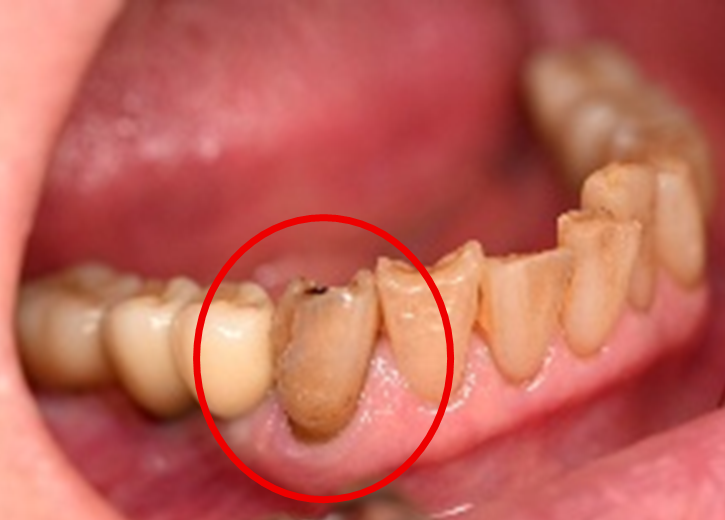

女性 Tさん 40代 (オールセラミック冠)

主訴

右上の被せものをしているところが、むし歯になり食べものがはさまるのでので、治したい。

治療内容

右下の歯が、根の先で問題を起こし、かつ歯周病でもありました。根管治療と歯周病治療をしました。

患者さんは、メタルフリーの治療を希望されましたので、ファイバーコアをいれオールセラミック冠を被せました。

所感

他院で抜歯を宣告された歯でした。根管治療と歯周病治療をすると腫れはなくなり残せると判断しました。歯のまわりの清掃の仕方をしっかり指導しました。患者さんは、丁寧に実践してくれています。

オールセラミック冠:¥86,400×1本=¥86,400